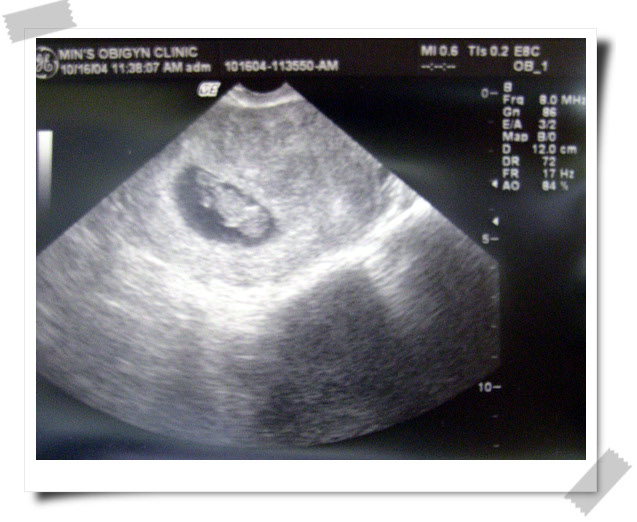

_ 아빠랑 시흔이와 함께 병원에서 아기를 보고왔다.

초음파로 보이는 작은 형체를 보며 시흔인 연실 '아기다~아기있네~'한다.

* 둘째 - 그새 제법 컸다. 2.5cm (예정일이 하루뒤인 05년 5월 19일로 잡힘)

* 혈류, 심장박동 정상 - 건강하게 잘크고 있단다.. 한달후 방문